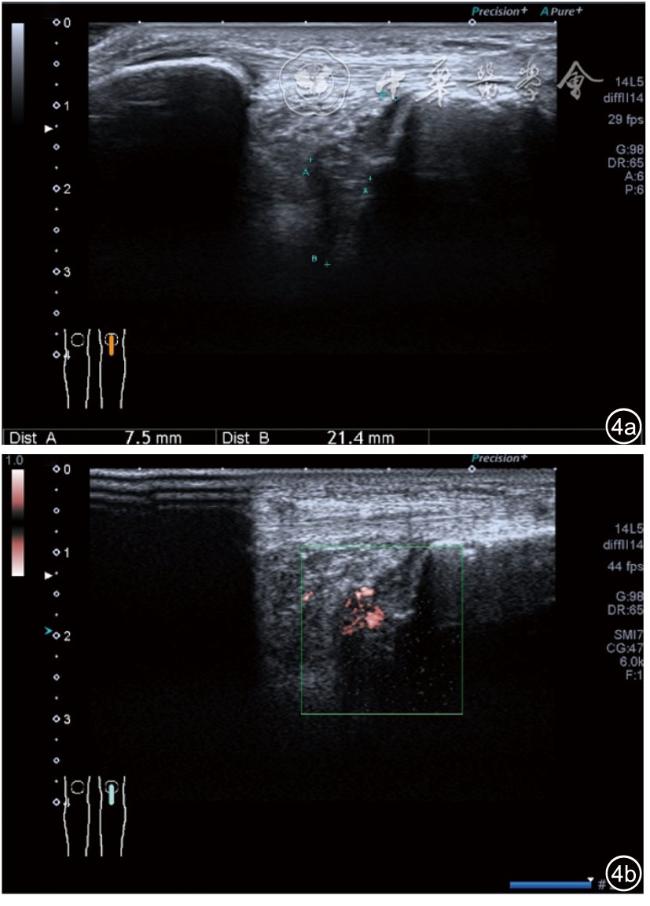

2.膝关节静态结构治疗。动力平衡失调后,继发静态结构变化,出现内外侧副韧带、交叉韧带、脂肪垫、半月板等结构变化。这里介绍半月板与交叉韧带的处理。(1)膝关节静态结构半月板治疗。在膝关节骨关节炎中主要是突出和损伤。突出主要发生于膝内翻引起的内侧半月板突出,引起内侧副韧带的张力增高。内侧半月板与内侧副韧带相连,是引起膝关节内侧疼痛的主要原因之一。治疗主要是针刀剥离松解,部分损伤可行PRP注射。①半月板突出针刀剥离松解治疗。针刀治疗主要是松解和减压,缓解疼痛,不能复位。以内侧半月板突出治疗为例。患者平卧位,髋轻度外展外旋,膝关节屈曲30°,膝下垫一软枕。选用10 MHz超声探头,穿刺区域常规消毒,探头涂抹耦合剂后套入无菌手套碘伏消毒或使用无菌耦合剂。将探头置于患者皮肤表面,内侧关节间隙长轴扫查,找到半月板突出最高点,用25G针头,抽吸1%利多卡因3 ml逐层麻醉直到半月板。选用直径1 mm的Ⅰ型2号针刀从头侧向足侧方向在内侧副韧带与半月板之间,以及半月板内部进行剥离松解3~5刀拔出针刀(图13),局部压迫5分钟,无菌敷料覆盖。②半月板损伤PRP注射治疗。半月板损伤主要表现为髌下痛,伸膝加重,查体在髌下髌韧带与侧副韧带之间,沿关节间隙有固定或局限性压痛,伸膝过程中尤为明显。MRI可示半月板断裂、损伤。如果出现绞索,严重影响功能需手术治疗。半月板损伤治疗,以注射PRP修复为主。以内侧半月板后角损伤为例。患者俯卧位,治疗前准备同半月板突出针刀剥离松解治疗。选用25G注射针头,抽取1%利多卡因2 ml局部麻醉后,制取1.5 ml PRP,穿刺到达半月板撕裂处注射,注射完毕后出针(图14),局部压迫2分钟,无菌敷料覆盖。(2)膝关节静态结构交叉韧带治疗。膝关节骨关节炎交叉韧带损伤多为部分损伤,治疗早期主要为药物或PRP注射,效果不佳时针刀做止点松解。①后交叉韧带损伤药物注射治疗。主要治疗韧带肿胀、无明显断裂患者。患者俯卧位,膝关节伸直位。一般选用10 MHz超声探头,治疗前准备同半月板突出针刀剥离松解治疗。将探头置于患者皮肤表面,后交叉韧带长轴扫查,找到胫骨止点,选用22G长针头,抽吸1%利多卡因3 ml+曲安奈德10 mg,从头侧向足侧方向穿刺到后交叉韧带胫骨止点部位的韧带表面进行注射,注射结束拔出针头(图15),局部压迫2分钟,无菌敷料覆盖。②前交叉韧带损伤PRP注射治疗。患者仰卧位,膝关节伸直。选用10 MHz超声探头,治疗前准备同半月板突出针刀剥离松解治疗。将探头置于患者皮肤表面,短轴扫查,找到前交叉韧带胫骨止点,选用25G针头,抽吸1%利多卡因3 ml逐层麻醉直到韧带止点部位,制备PRP 3 ml注射到前交叉韧带显露部位,注射结束拔出针头(图16),局部压迫2分钟,无菌敷料覆盖。③前交叉韧带损伤针刀剥离松解治疗。体位与治疗前准备同前交叉韧带损伤PRP注射治疗。短轴扫查找到前交叉韧带胫骨止点,选用25G针头,抽吸1%利多卡因3 ml逐层麻醉直到韧带止点部位,选用直径0.6 mm的Ⅰ型2号针刀从外侧向内侧于前交叉韧带胫骨止点部位剥离松解3~5刀拔出针刀(图17),局部压迫5分钟,无菌敷料覆盖。

图14 超声引导下半月板损伤富血小板血浆注射治疗

图4 交叉韧带损伤超声图像